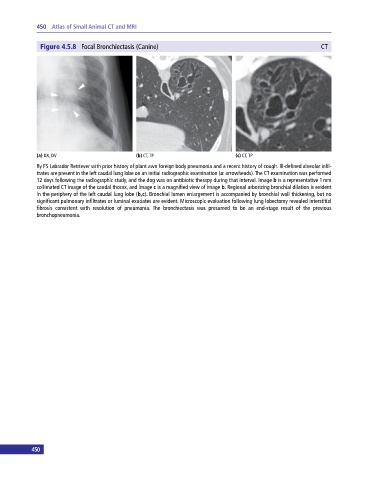

Figure 4.5.8 Focal Bronchiectasis (Canine) CT

(a) DX, DV (b) CT, TP (c) CT, TP

8y FS Labrador Retriever with prior history of plant awn foreign body pneumonia and a recent history of cough. Ill‐defined alveolar infil

trates are present in the left caudal lung lobe on an initial radiographic examination (a: arrowheads). The CT examination was performed

12 days following the radiographic study, and the dog was on antibiotic therapy during that interval. Image b is a representative 1 mm

collimated CT image of the caudal thorax, and image c is a magnified view of image b. Regional arborizing bronchial dilation is evident

in the periphery of the left caudal lung lobe (b,c). Bronchial lumen enlargement is accompanied by bronchial wall thickening, but no

significant pulmonary infiltrates or luminal exudates are evident. Microscopic evaluation following lung lobectomy revealed interstitial

fibrosis consistent with resolution of pneumonia. The bronchiectasis was presumed to be an end‐stage result of the previous

bronchopneumonia.